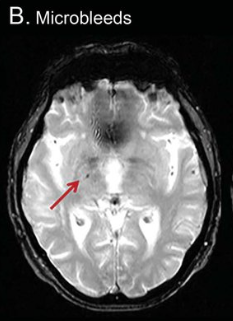

Visualizing SVD with a brain scan

Not everything can be visualized with a brain scan. For example, the small blood vessels are not visible on a scan, but the brain damage in the form of microbleeds in the cerebrum or abnormalities in the white matter are. These are called 'white matter hyperintensities'. 'Lacunar (very small) infarctions and other subcortical infarctions (under the cerebral cortex) can also be visible. Furthermore, the spaces between the walls of blood vessels and the white matter of the brain can be visible; these are the 'perivascular spaces'. C-reactive protein (CRP) can be elevated in the blood. This is a non-specific indication of inflammation somewhere in the body. CRP is predictive of SVD and is elevated when the condition is really obvious.

It was shown that people with moderate or severe white matter hyperdensity (WMH) had a high chance of increasing their SVD, while participants with mild SVD showed a mild increase over a period of 9 years. In 3.6% of the study participants, the lacunae disappeared and in 5.7% of the participants, the microbleeds disappeared, but the white matter hyperdensities could increase.

See the images of the study od Radboud University Nijmegen